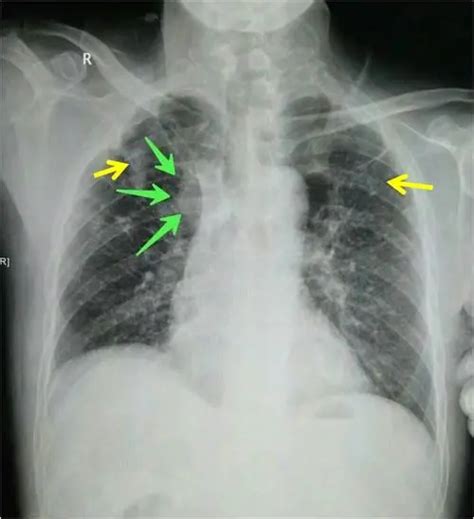

首先啊,三型肺结核,确实是有传染性的,这一点咱们得承认。它主要通过飞沫传播,比如病人咳嗽、打喷嚏的时候,那些看不见的小飞沫里就可能藏着病菌。所以,如果你身边有这样的人,确实需要多加小心,保持一定的距离,戴好口罩,这些都是保护自己的好方法。

但是,也别太紧张了。现在的医学技术那么发达,治疗肺结核的药物也是越来越有效。只要病人按时吃药,积极治疗,传染性是可以大大降低的。而且,我们的身体也有自己的防御机制,不是说一接触就会被传染的。